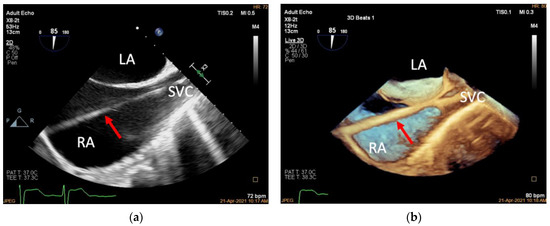

3.2. Introducing the Delivery System (Mid-Esophageal Bicaval View)